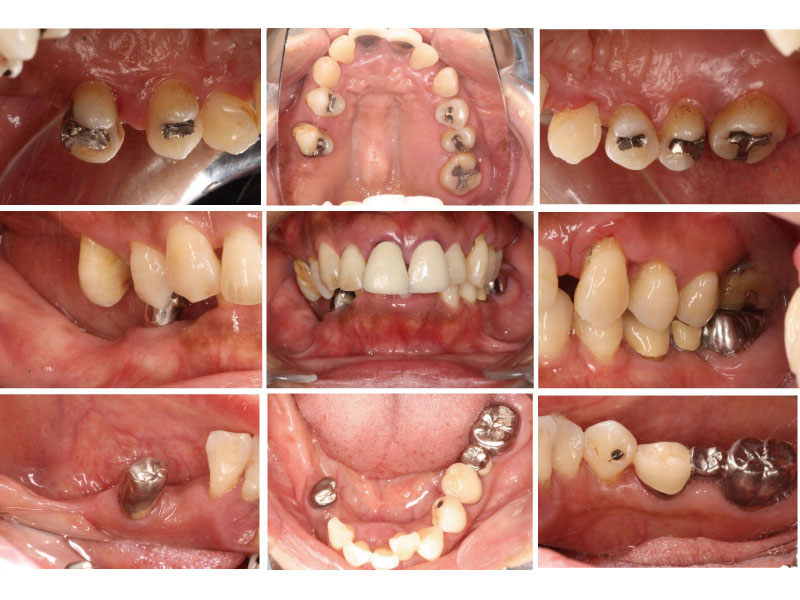

治療前口腔内写真